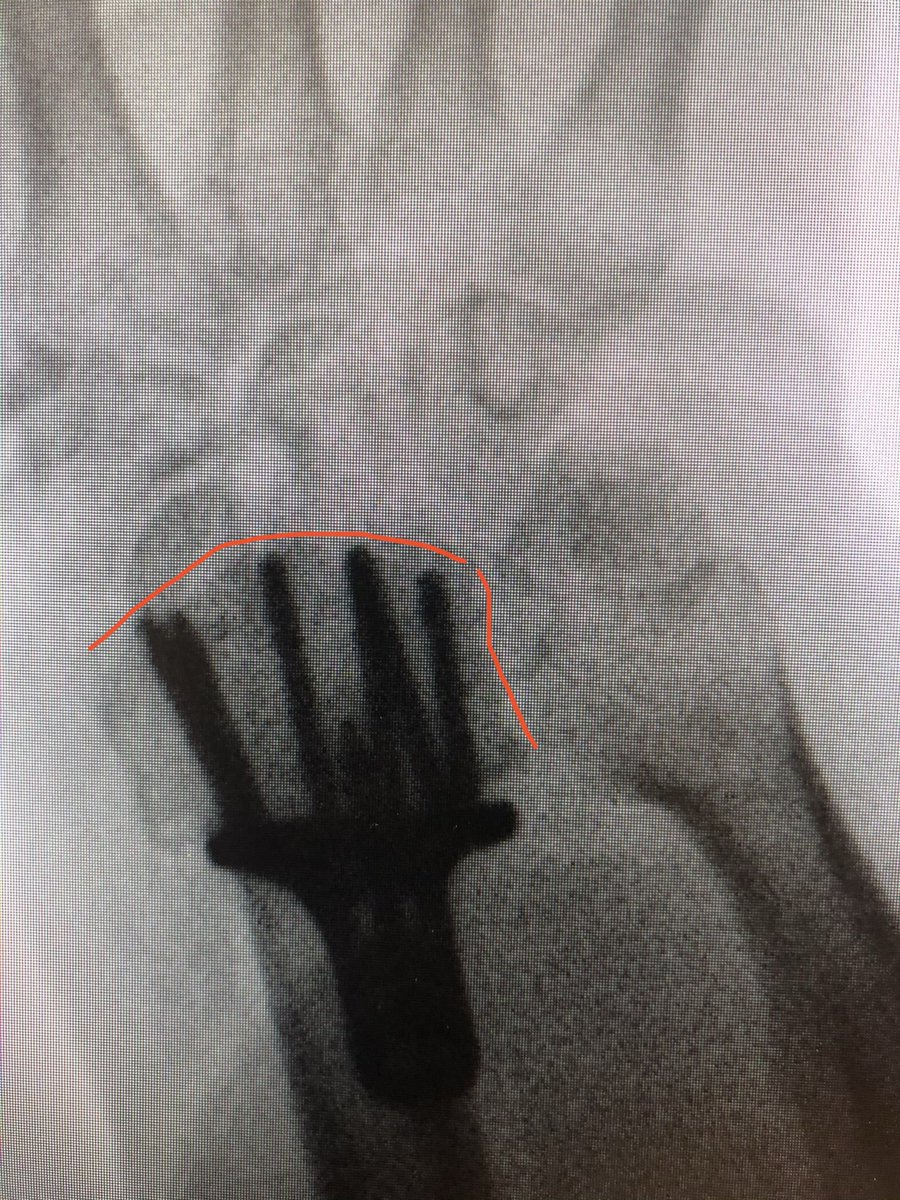

This was the patient at 2 weeks. Already on range of motion. The flat lateral X-ray always looks like the screws are in the joint. That’s because of the distal radius joint inclination angle.

Take intra-operative 20 degree elevated lateral shot to see through the joint.